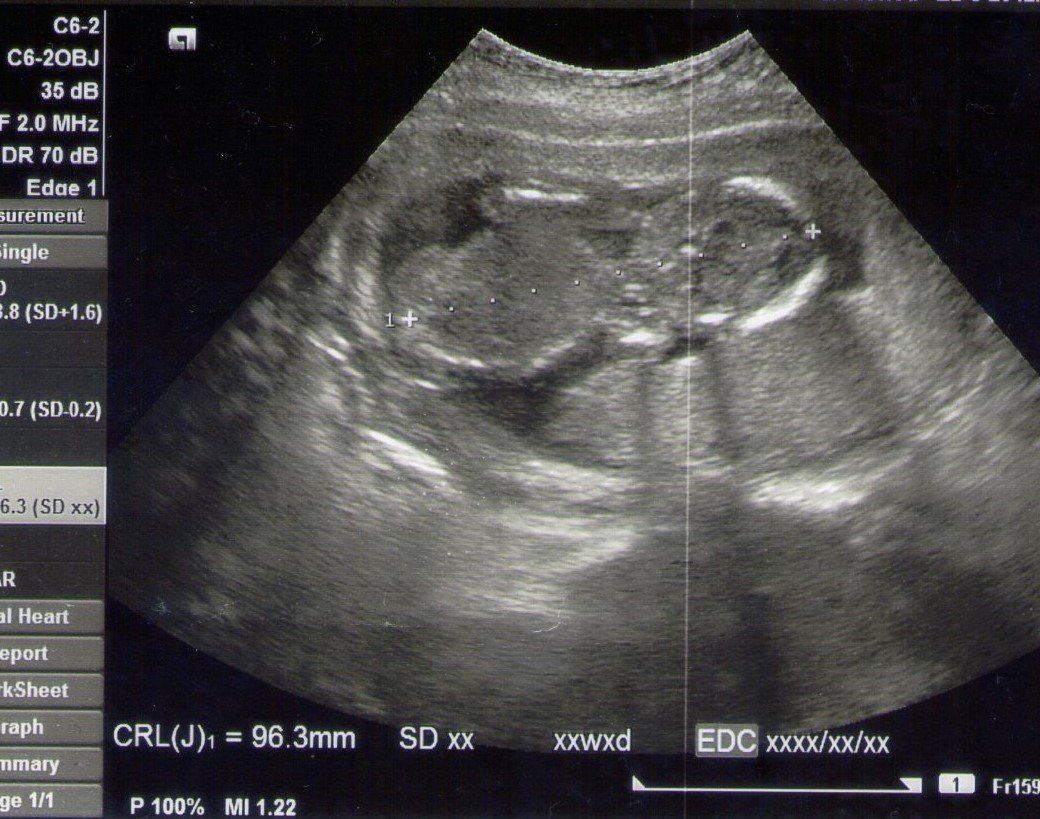

妊娠16週目のエコー写真 初めておなかでエコー

CRL=96.3㎜

赤ちゃんが横向きに写っています。頭は右側で左側がお尻です。赤ちゃんの心臓の動きが、ものすごく早くて驚きました。大人の2倍くらい速い動きだと聞きました。初めて胃と膀胱が確認できました。骨も太くなり、順調に成長していてほっとしました。次の日に初めて胎動を感じました。赤ちゃんが動くと、グニャ、ポコ、グリというような動きが感じられてビックリ! 自分のおなかも大きくなってきて、おへそが横長になってしまいました。